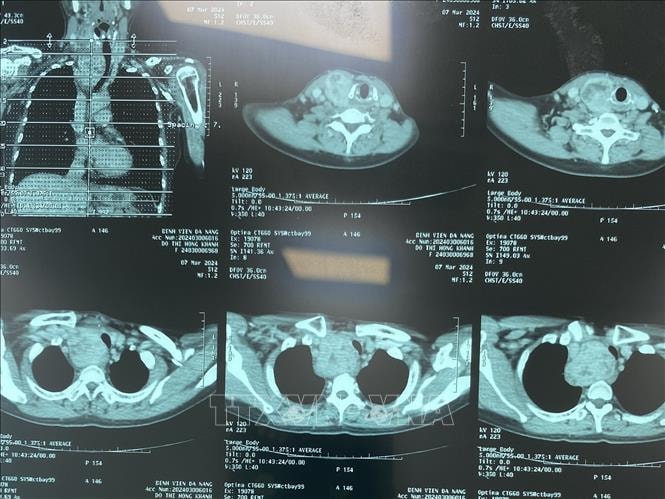

Chẩn đoán hình ảnh không cần phim in vào Quỹ BHYT chi trả

Theo Quyết định số 313/QĐ-BYT mới đây của Bộ Y tế, Bệnh viện Bạch Mai là đơn vị đầu tiên của ngành y tế được phê duyệt giá dịch vụ kỹ thuật chẩn đoán hình ảnh sử dụng hệ thống lưu trữ và truyền tải hình ảnh (PACS) thuộc phạm vi thanh toán của quỹ BHYT.